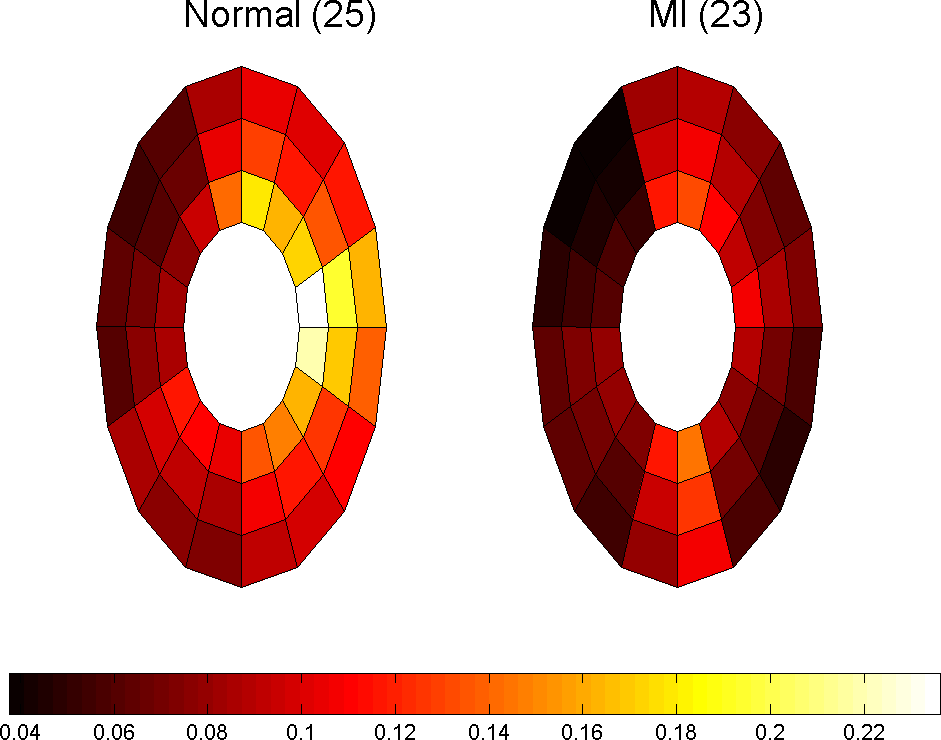

which in 2D case can be simplified because . Using this parameter we are able to monitor the changes in strain maps of heart muscle during deformation. Computing effective strain values for different slices of cardiac muscle, these values are used for comparison between healthy and MI subjects. Fig. 10 represent the results for first slice of healthy subjects, 18 and 25, and MI subject 23 during the cardiac cycle.

Fig. 11 shows the approximate infarct localization for the MI subject based on the comparison between normal and MI subjects’ effective strain during the cardiac cycle. Since the circulatory system of heart is determined very well, it is possible to make reliable conclusions about the problem that caused MI based on expert diagnosis and using these comparisons.